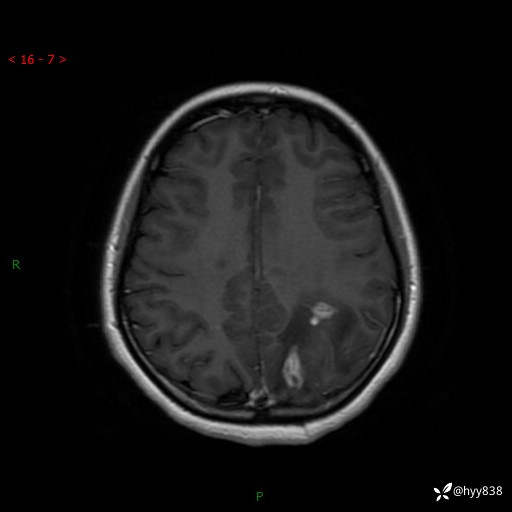

颅脑MRI平扫+增强